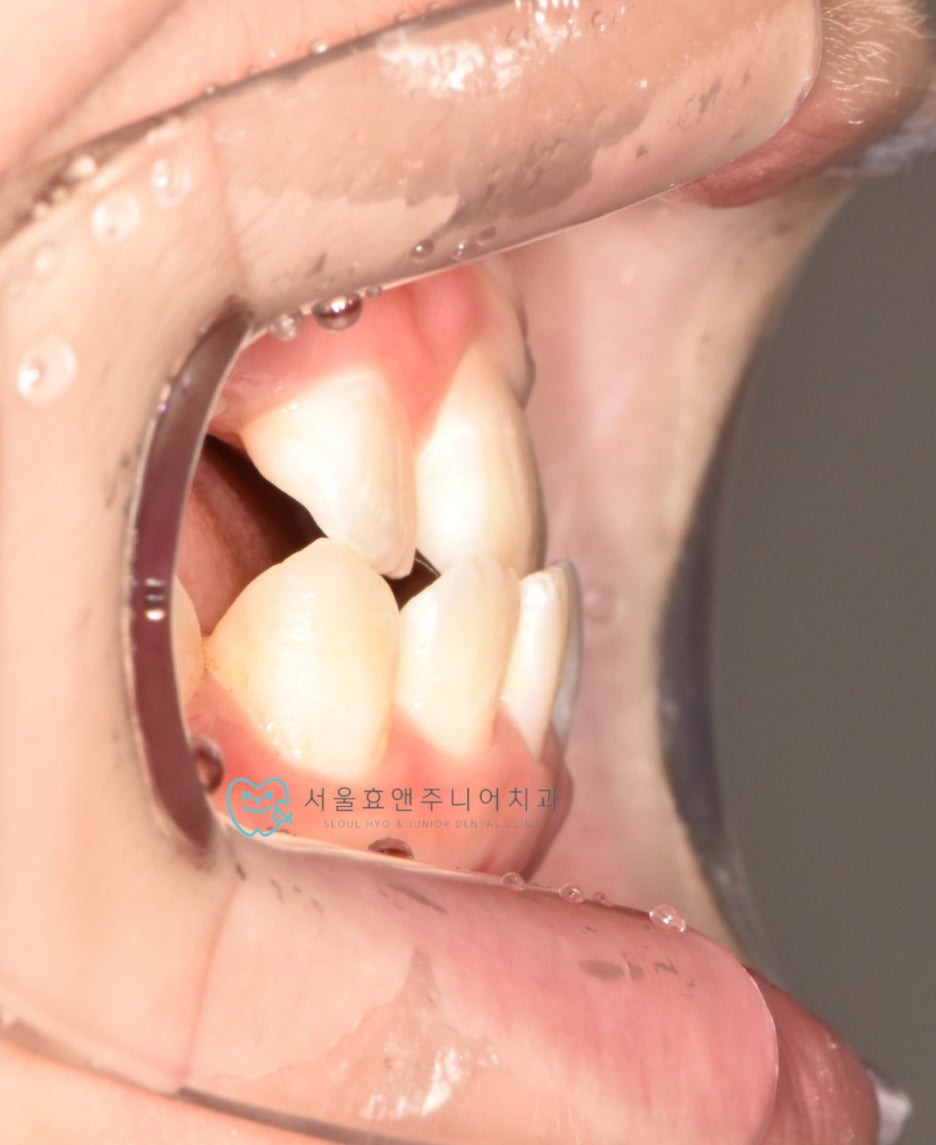

초진사진입니다

초진사진입니다. 11세 5개월 환아로, 반대교합을 보이고 있습니다. 반대교합으로 인해 치아가 부딪혀 치은퇴축(잇몸이 내려감)도 보이고 있네요.(화살표)